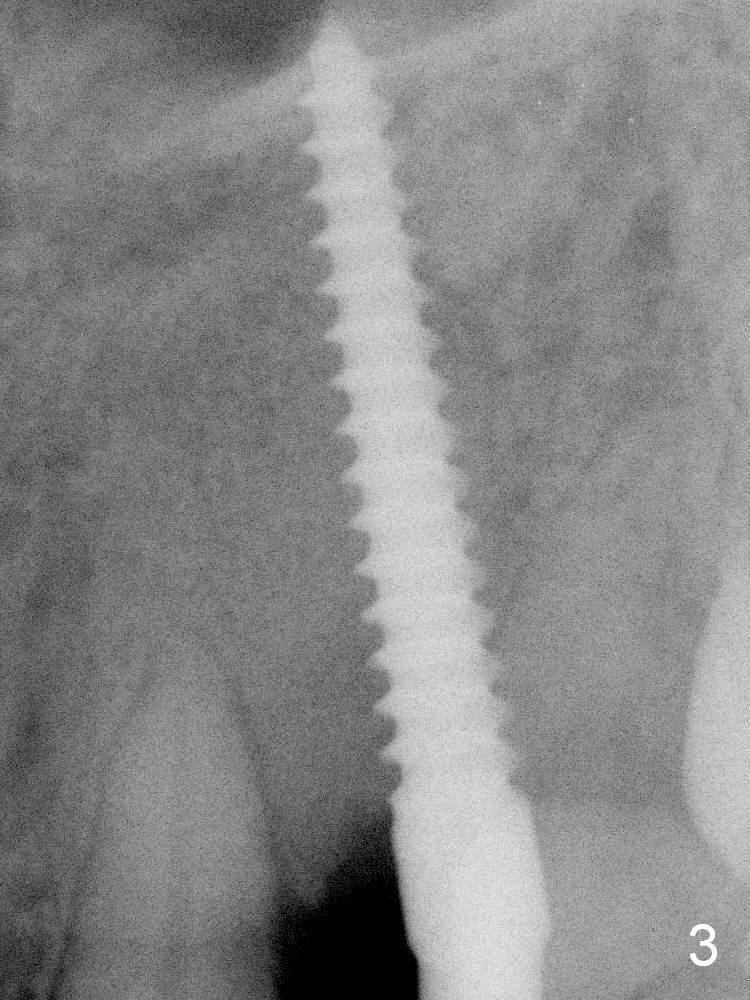

Intraop PA shows that the nasal floor is apparently perforated (Fig.3). In fact the transverse cortical plate is the horizontal plate of the palatine bone.